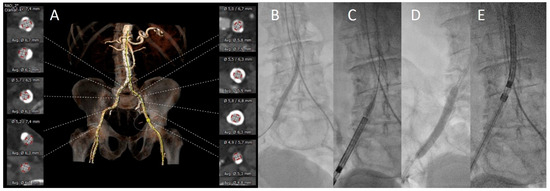

3.2. Vascular Assessment

3.3. Procedural Aspects